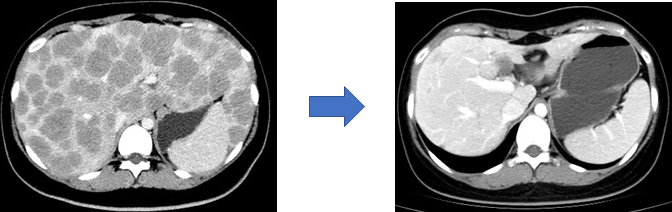

文献报道约60%的神经内分泌肿瘤发现时已属中晚期,直接手术治疗效果不佳。目前多采用药物转化治疗。经过药物治疗后肿瘤负荷降低、范围及体积缩小,在联合手术治疗可进一步改善患者预后(图7,8)。常用的转化治疗手段包括靶向药物治疗、化疗、介入治疗及PRRT等。

图8

66岁男性患者,因胰腺体尾部巨大占位入院,穿刺活检提示大细胞型神经内分泌癌(左图),予IP方案(伊立替康+卡铂)新辅助化疗6次,肿瘤显著缩小(右图),降期成功并行根治性手术。